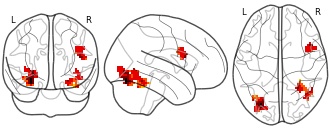

"name": "Multi_VBMsmaller_fMRIenhanced",

"description": "Multi-modal analysis in BPD. Brain regions exhibiting smaller gray matter and enhanced activation during emotion processing in BPD compared to healthy controls. Note: Results were thresholded at p<.0025. Note2: Results were updated (see Erratum for this publication).",